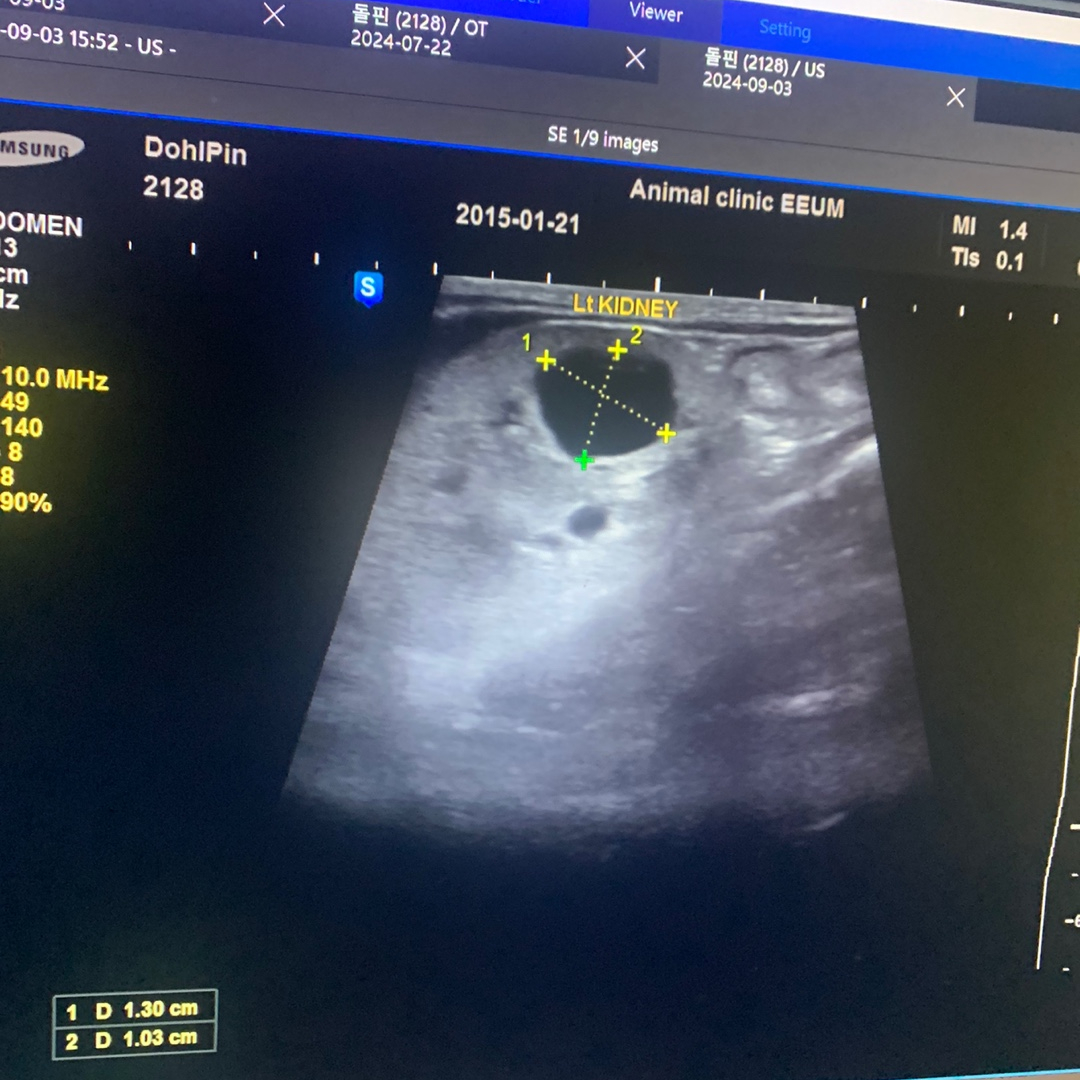

🐈 돌핀(9세, 2.3kg)은 다낭성 신부전(PKD)뿐만 아니라 과민성 대장 증후군, 관절염을 함께 앓고 있는 고양이 입니다. 돌핀은 AIM 활성화를 목표로 '닥터토루 프로토콜'을 3개월 동안 꾸준히 섭취했고, 이 기간 동안 초음파 검사를 통해 왼쪽 신장의 낭종 크기가 2.5cm에서 1.5cm로 감소하는 것이 확인되었습니다. 또한, 활력이 증가하여 이전에는 잠만 자던 돌핀이 다양한 의사 표현을 하며 간식과 사료를 자주 조르는 등의 변화를 보였습니다.